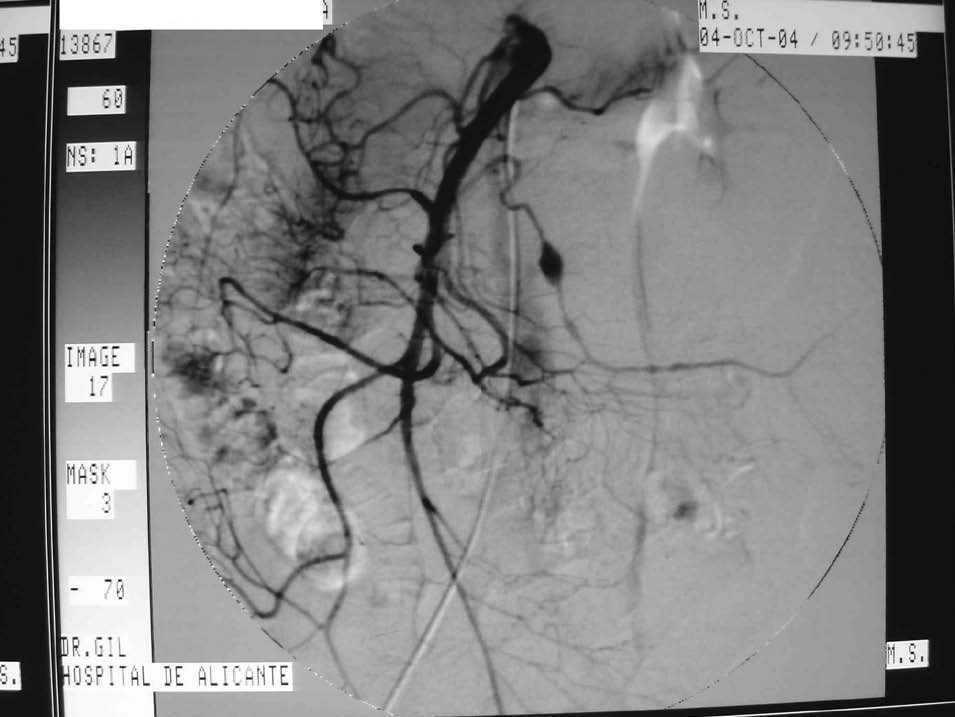

La analítica puso de manifiesto una leucocitosis (24,7 * 103/ul) y una anemia (hemoglobina 8,9 g/dl y hematócrito del 29%). Se le realizó un tomografía computarizada abdominopélvica en la que se describió una doble lesión quística pediculada dependiente de curvatura mayor gástrica, de 4,8 * 2,9 * 7,8 cm la lesión superior y 3,2 * 2 * 4,5 cm la lesión inferior, sugestiva de lesión neoplásica mesentérica (probable linfoma) o hematoma organizado (fig. 1). Se realizó una punción-aspiración con aguja fina (PAAF) de la lesión obteniéndose material sanguinolento. Se realizó una colonoscopia, y se observó una colitis isquémica segmentaria de colon. La resonancia magnética de abdomen y pelvis mostró una tumoración en la región epigástrica que ocupaba la transcavidad de los epiplones. Se realizó una arteriografía visceral selectiva, observándose una dilatación aneurismática de una rama de la arteria mesentérica superior que presentaba distalmente un calibre irregular con segmentos también dilatados (fig. 2).

Fig. 2. Angiografía. Aneurisma de rama de arteria mesentérica superior.